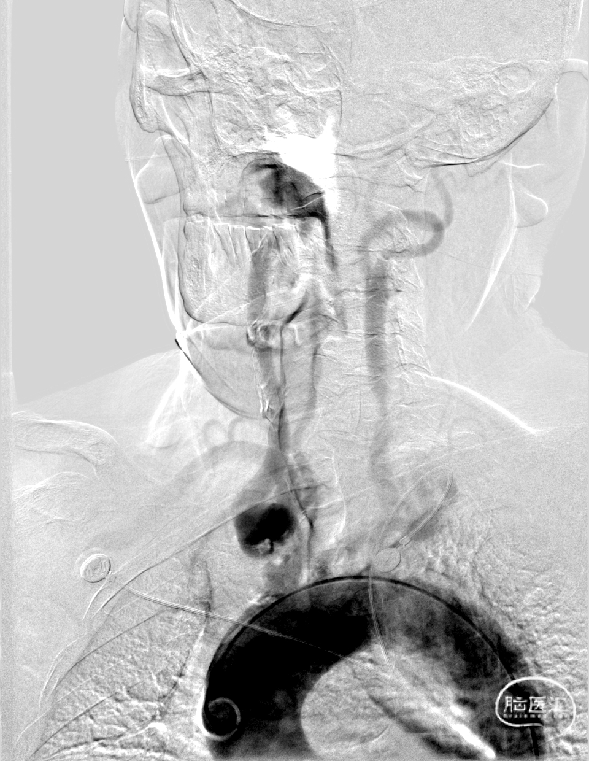

DSA:经股动脉行主动脉弓造影显示:二型弓,头臂干可见充盈缺损,头臂干分叉处迂曲。

对比CTA提示经桡入路选择右侧颈总动脉较困难。

125cm MPA配合泥鳅导丝选入右侧锁骨下动脉内,同轴技术跟进NeuronMAX至头臂干起始处造影可见血栓影。

支架释放后造影可见支架完全覆盖血栓,位置良好,椎动脉血流缓慢,可能有血栓脱落。

半回收保护伞依次回收颈动脉保护伞和椎动脉保护伞。

颈内动脉和椎动脉保护伞都发现血栓。

取出保护伞后椎动脉流速恢复正常,颅内未发现明显的大血管栓塞。